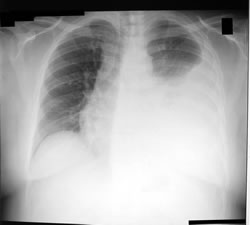

Derrame pleural: El liquido pleural es un fluido filtrado del plasma sanguíneo que se encarga de amortiguar los movimientos respiratorios entre las pleuras parietal y visceral (envoltorio del pulmón). La acumulación anormal es debido a la falta de drenaje, a la disminución de las proteínas de la sangre, a la falla cardiaca, a la falla renal, la falla hepática, las infecciones pulmonares, entre otros. Los síntomas principales son: dificultad respiratoria y dolor con la respiración en un costado o en la espalda.